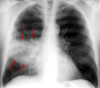

What does a perforated bowel look like on x-ray?

Space below the diaphragm and maybe some inflammation as commensals from bowel have leaked out